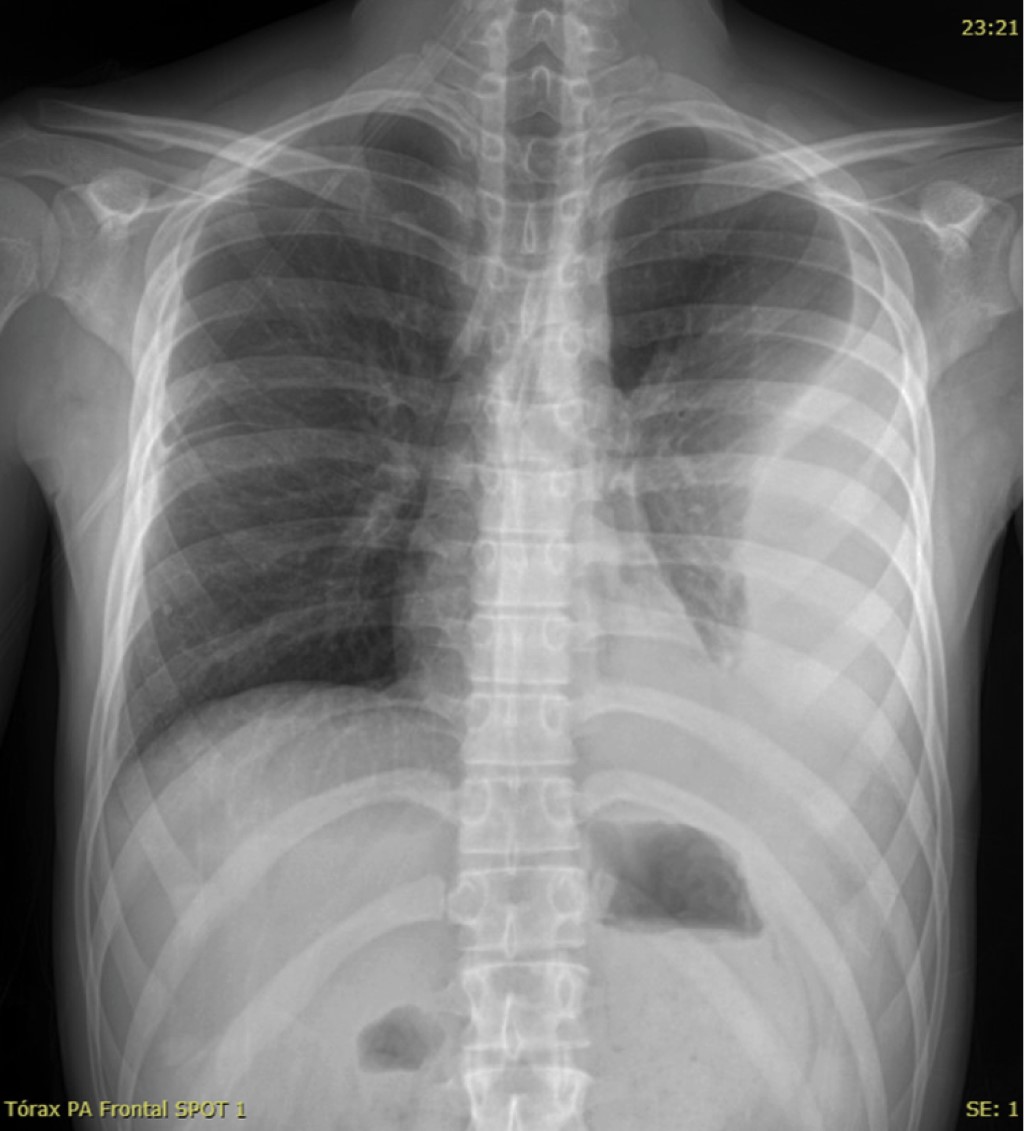

La exploración radiológica habitual del tórax consiste en la realización de dos proyecciones: posteroanterior (PA) y lateral izquierda (L). Se realizan con el paciente en bipedestación o sedestación, la PA a una distancia foco-película de 1.8 metros y la lateral izquierda a 2 metros.

En pacientes con mal estado clínico, lactantes y pacientes poco cooperadores, frecuente en la edad pediátrica, se realizan radiografías en proyección anteroposterior (AP) y con equipos portátiles, con el inconveniente de obtener imágenes de baja calidad técnica, dado que esta proyección se realiza a menor distancia foco-película, magnifica las estructuras y se obtienen imágenes menos nítidas.5

Existen otras proyecciones radiológicas como son: la radiografía en espiración, la cual detecta pequeños neumotórax y atrapamiento aéreo localizado asociado a cuerpos extraños; la proyección en decúbito lateral con rayo horizontal que evalúa líquido libre en la cavidad pleural, entre otras.